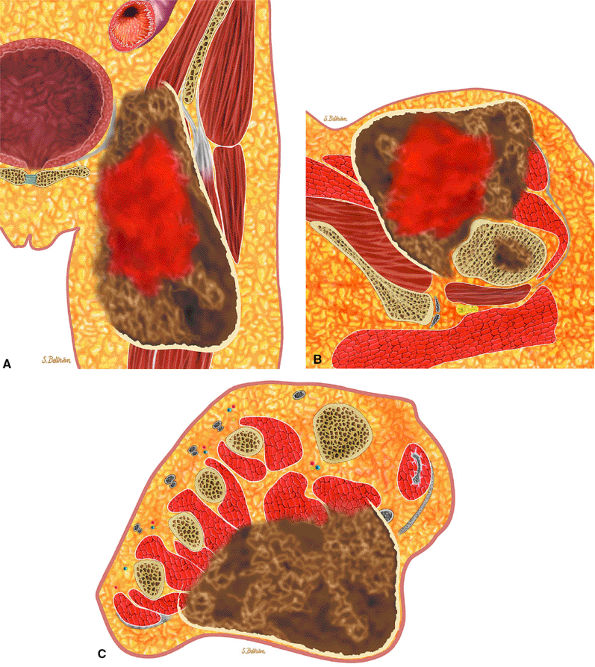

FIGURE 14-74 ● Chondrosarcoma of the proximal femur (A) and calcaneus (B). Chondroid tissue is shown in blue. Note cortical destruction and soft-tissue extension.

centrally, are composed of characteristic lobules of gray-white translucent tissue with spotty calcification.61 The adjacent cortex may be thickened or eroded, with extension of the neoplasm into the surrounding soft tissues.